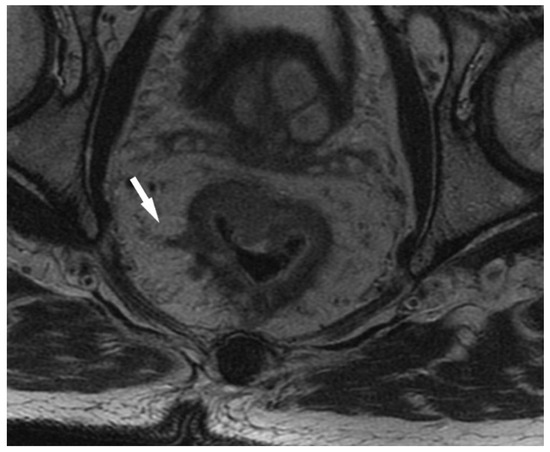

2.2. Assessment of Status of EMVI

- Inoue, A.; Sheedy, S.P.; Heiken, J.P.; Mohammadinejad, P.; Graham, R.P.; Lee, H.E.; Kelley, S.R.; Hansel, S.L.; Bruining, D.H.; Fidler, J.L.; et al. MRI-detected extramural venous invasion of rectal cancer: Multimodality performance and implications at baseline imaging and after neoadjuvant therapy. Insights Imaging 2021, 12, 110. [Google Scholar] [CrossRef]